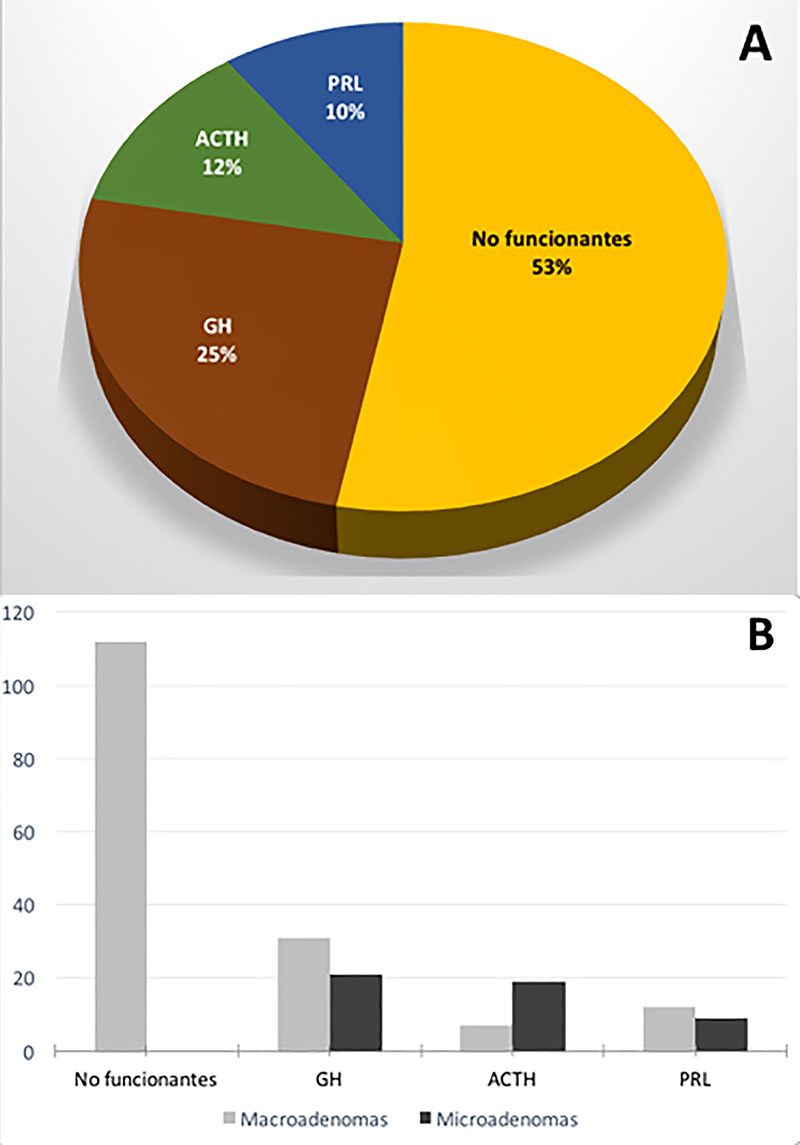

En base a su presentación clínica y de laboratorio, un 47% (n=99) de los pacientes presentaron adenomas funcionantes y un 53% (n=112) no funcionantes. El 47% de adenomas funcionantes presentaron la siguiente distribución: 25% eran acromegálicos (n=52), 12% enfermedad de Cushing (n=26), y 10% prolactinomas (n=21) (graf. 1).

Gráfico 1: Resultados generales de la serie. A: Distribución de la población según tipo de patología. B: Distribución de la población considerando patología y tamaño tumoral.

Basados en la RM preoperatoria la serie consta con 76% (n=162) macroadenomas y 24% (n=49) microadenomas. Un 38% (n=80) fueron subclasificados con un alto grado en la clasificación de Knosp (grado 3 o 4).